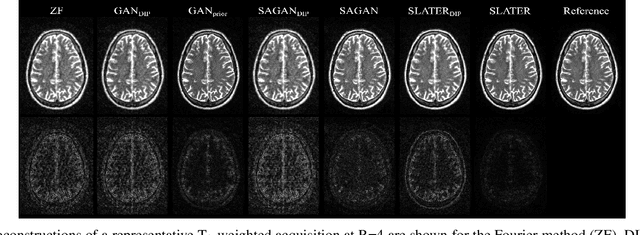

Supervised deep learning has swiftly become a workhorse for accelerated MRI in recent years, offering state-of-the-art performance in image reconstruction from undersampled acquisitions. Training deep supervised models requires large datasets of undersampled and fully-sampled acquisitions typically from a matching set of subjects. Given scarce access to large medical datasets, this limitation has sparked interest in unsupervised methods that reduce reliance on fully-sampled ground-truth data. A common framework is based on the deep image prior, where network-driven regularization is enforced directly during inference on undersampled acquisitions. Yet, canonical convolutional architectures are suboptimal in capturing long-range relationships, and randomly initialized networks may hamper convergence. To address these limitations, here we introduce a novel unsupervised MRI reconstruction method based on zero-Shot Learned Adversarial TransformERs (SLATER). SLATER embodies a deep adversarial network with cross-attention transformer blocks to map noise and latent variables onto MR images. This unconditional network learns a high-quality MRI prior in a self-supervised encoding task. A zero-shot reconstruction is performed on undersampled test data, where inference is performed by optimizing network parameters, latent and noise variables to ensure maximal consistency to multi-coil MRI data. Comprehensive experiments on brain MRI datasets clearly demonstrate the superior performance of SLATER against several state-of-the-art unsupervised methods.